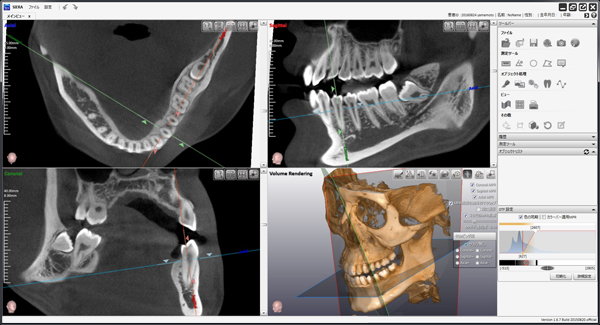

当院では、通常の二次元的なレントゲン撮影に加えて必要不可欠と判断した症例においては、必ず「歯科用CT」による撮影を行います。

歯科用CTを用いることで次のような情報を、ミリ単位で正確に把握することができます。

- 親知らずの根の形や本数、湾曲の度合い

- 顎の骨の中での親知らずの正確な位置と傾き

- 親知らずの根の先端と下歯槽神経との三次元的な位置関係

CTによる事前の詳細なシミュレーションは、手術中の偶発的な事故(神経の損傷など)のリスクを限りなくゼロに近づけより安全で確実な抜歯を可能にするための、いわば「手術の設計図」となる極めて重要なプロセスです。

検査で得られたCT画像などをお見せしながら、現在の親知らずがどのような状態にあるのか、なぜ抜歯が必要なのかそしてどのような手順で抜歯を行うのかを、専門用語を避けて分かりやすくご説明いたします。